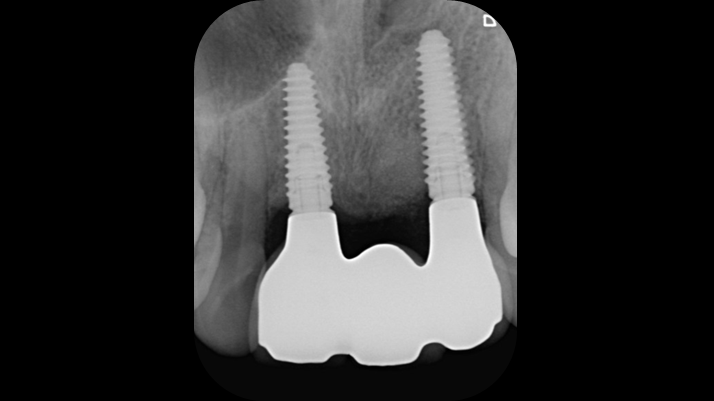

Clinical case: BPET PREDICTABILITY - State-of-the-Art SOCKET SHIELD

- Courtesy of Dr. Howard Gluckman, South Africa -

Socket Shield Technique, anterior esthetics, maxillary anterior, esthetic, esthetics, AnyRidge, Root Membrane Kit, Root Membrane Technique, Partial Extraction Therapy, PET, esthetic zone , Dr. Howard Gluckman

AnyRidge implant system, Root membrane kit, PET Kit